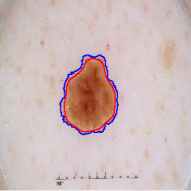

A few existing segmentation label noise approaches (Zhu et al., 2019; Zhang et al., 2020b; a) directly apply methods in classification label noise. However, these methods assume the label noise for each pixel is i.i.d. (independent and identically distributed). This assumption is not realistic in the segmentation context, where annotation is often done by brushes, and error is usually introduced near the boundary of objects. Regions further away from the boundary are less likely to be mislabeled (see Fig. 1(c) for an illustration). Therefore, in segmentation tasks, label noise of pixels has to be spatially correlated. An i.i.d. label noise will result in unrealistic annotations as in Fig. 1(b).

We propose a novel label noise model for segmentation annotations. Our model simulates the real annotation scenario, where an annotator uses a brush to delineate the boundary of an object. The noisy boundary can be considered a random yet continuous distortion of the true boundary. To capture this noise behavior, we propose a Markov process model. At each step of the process, two Bernoulli variables are used to control the expansion/shrinkage decision and the spatial-dependent expansion/shrinkage strength along the boundary. This model ensures the noisy label is a continuous distortion of the ground truth label along the boundary, as shown in Fig. 1(c). Our model also includes a random flipping noise, which allows random (yet sparse) mislabels to appear even at regions far away from the boundary.